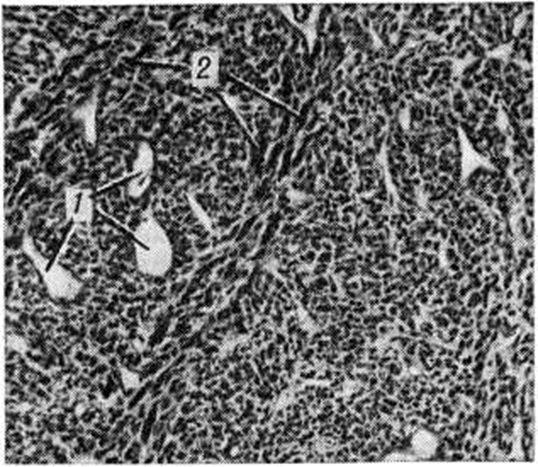

При микроскопическом исследовании наблюдается полиморфизм клеток; среди клеток преобладают веретенообразные формы, наблюдается обилие фигур деления (рисунок 2), прорастание клеток в просвет сосудов, инфильтрация окружающих тканей. Отличается агрессивным ростом, часто метастазирует (до 15% в регионарные лимфатических, узлы и до 50% в лёгкие) и рецидивирует (в 40—50% случаев).